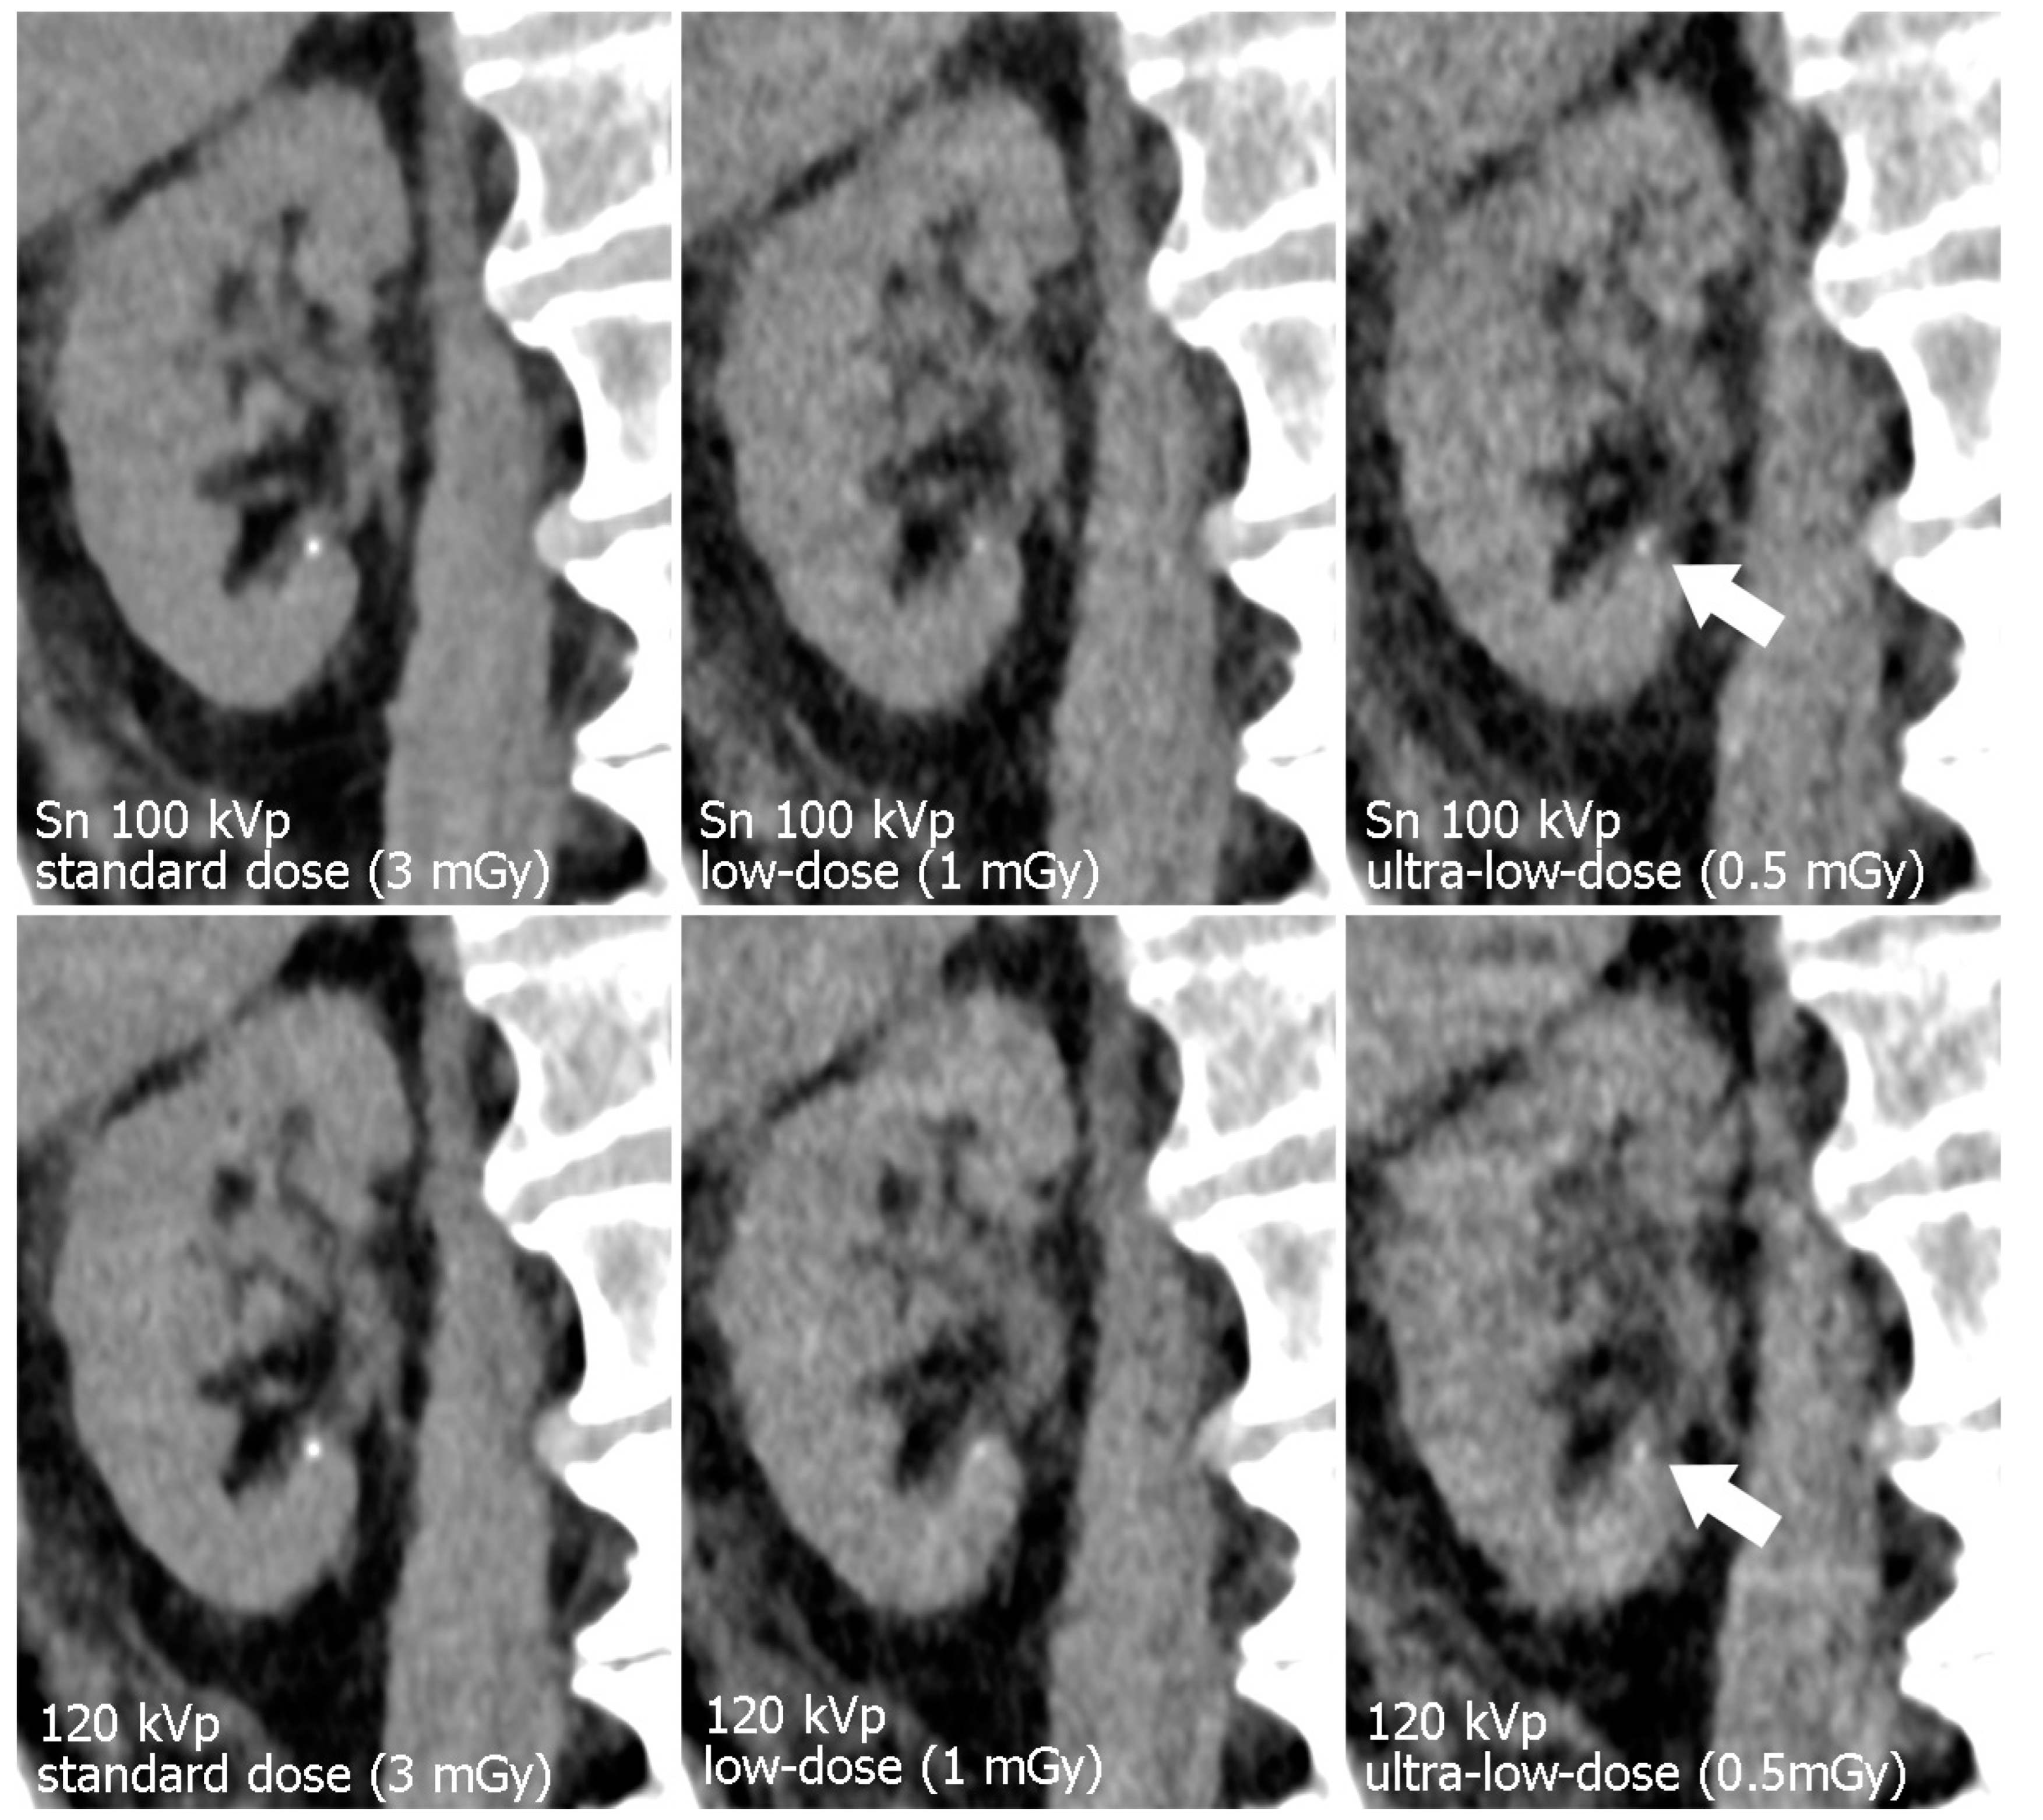

CTDIvol showed minor variations between specimens, as is to be expected with activated automatic tube modulation and different constitutions of the cadaveric specimens. The standard-dose tin-filtered protocol was associated with a mean CTDIvol of 3.38 ± 0.53 mGy, while the respective polychromatic scan protocol resulted in a mean CTDIvol of 3.53 ± 0.62 mGy (p = 0.108). Referring to the low-dose level, mean CTDIvol of Sn 100 kVp examinations was lower than of polychromatic 120 kVp scans (1.12 ± 0.18 vs. 1.21 ± 0.21 mGy; p = 0.007). For ultra-low-dose studies, tin prefiltration resulted in a mean CTDIvol of 0.55 ± 0.09 mGy, whereas polychromatic imaging produced a matching radiation dose of 0.56 ± 0.09 mGy (p = 0.168). Table 2 provides a detailed display of individual dose parameters per specimen. Figure 3; Figure 4 illustrate the effects of dose reduction and spectral shaping regarding demarcability of kidney organ structures and detection of urinary calculi.

Figure 3.

Para-coronal images displaying the left kidney. The renal pelvis is not dilated but pelvic structures remain assessable even in ultra-low-dose images. Note the increased noise in the 120 kVp ultra-low-dose study compared to the dose-matched protocol with tin filtration.

Figure 4.

Para-coronal images of the right kidney display a minuscule calcification (arrow). Note the decrease in image quality with lower radiation dose. Organ margins and the calcification appear sharper with tin filtration ultra-low-dose imaging.